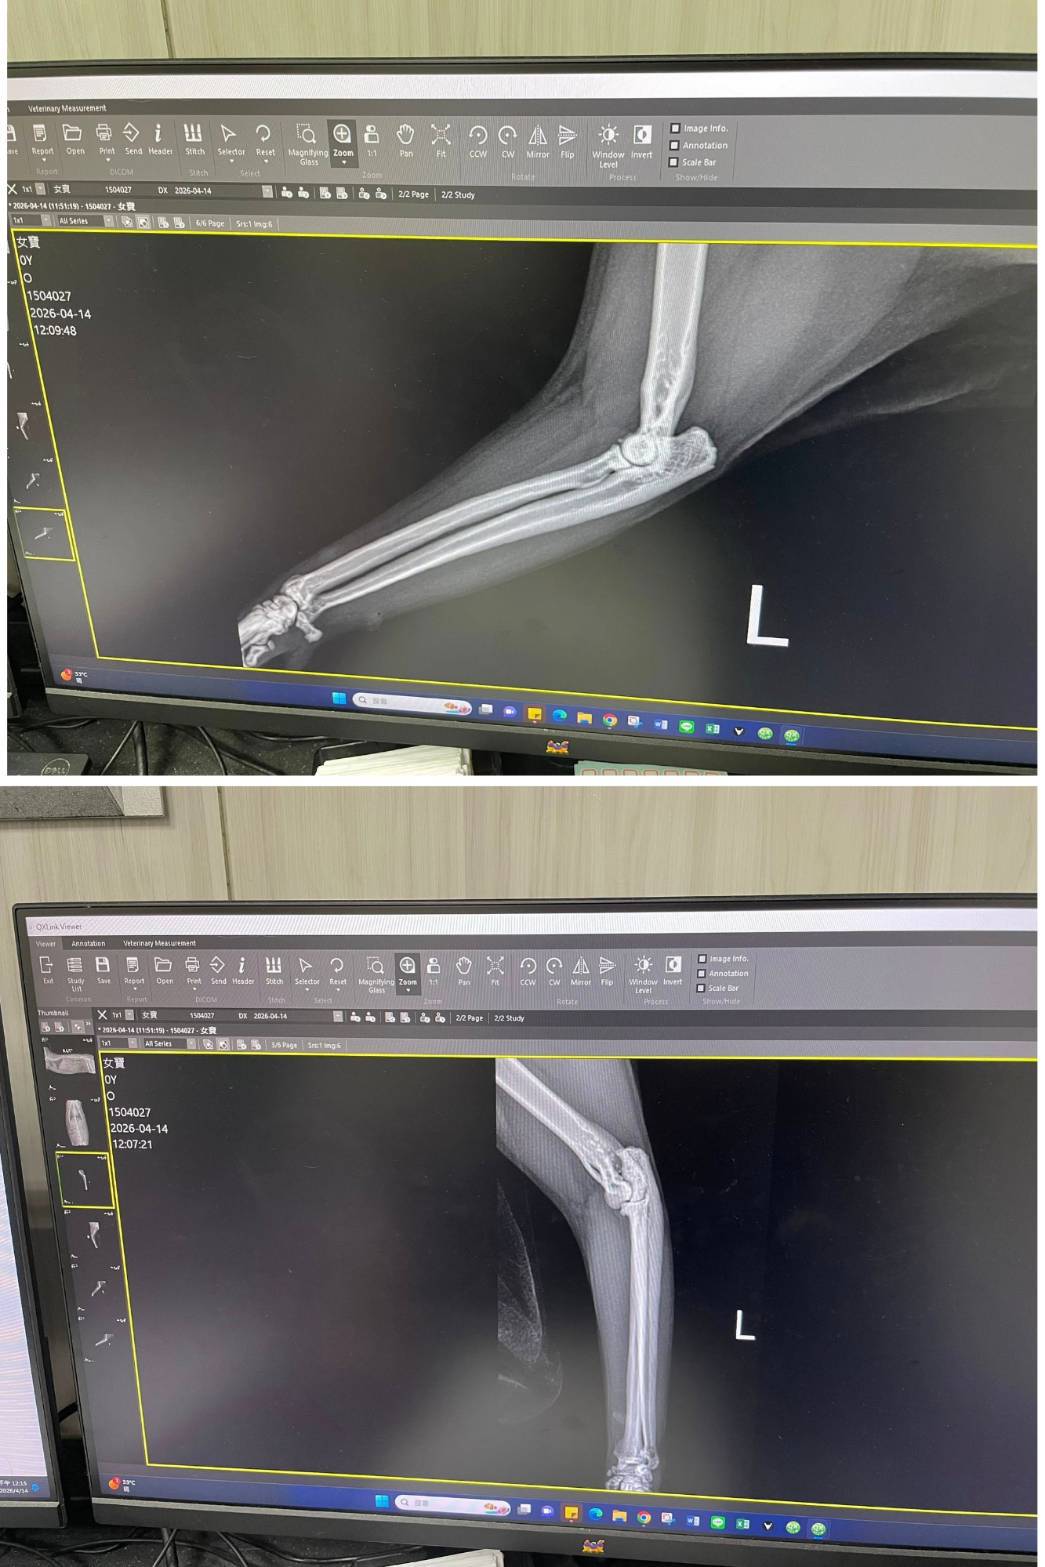

經X光檢查發現右前肢骨骼退化較嚴重,左邊也有一點骨骼退化;肺功能也是偏差;有牙周炎、牙齦萎縮所以齒根比較出來。X光有拍到兩顆東西,穿刺抹片檢查,淋巴細胞正常,淋巴結腫大。於醫院先點一錠除,並開立內用驅蟲藥,三個月後體外驅蟲需要再做一次。目前已於14日當日就醫後先行安置於協會幾日,因考量女寶年齡已大,汐止愛媽會帶回家中安置給女寶一個長久安穩的家。本筆醫助是女寶2026年4月14日於沐恩醫院看診的費用,包含血檢、X光、三合一、心臟快篩、皮膚抹片、一錠除滴劑及驅蟲藥。

右前肢比較嚴重左邊也有一點骨骼退化。